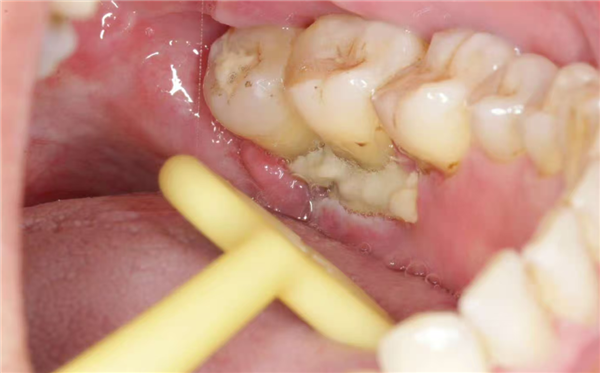

1、残根牙冠

比如很多人嘴里有残根残冠(烂到牙根无法治疗保留的牙齿、经久不治长期发炎肿包的病牙),这些牙齿周围本就藏着大量细菌,虽然可能只是偶尔疼一下,也没有特别的疼痛不适;但因为进行了化疗等肿瘤药物治疗后,口腔黏膜变得脆弱,细菌容易突破黏膜屏障,就可能会引发口腔溃疡、急性牙髓炎、根尖周炎、牙龈炎、牙周炎、智齿冠周炎等,甚至扩散成全身引发严重的感染(如败血症)。

一旦出现严重的感染,不仅要暂停肿瘤治疗(比如推迟化疗),还得用抗生素等药物控制感染,既耽误治疗进度,错过最佳治疗时机,又增加身体的痛苦,更打击患者抗癌的斗志。